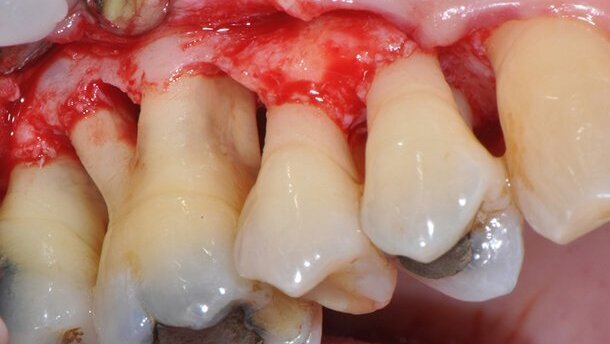

La rivalutazione eseguita a un mese dalla OSFMI ha evidenziato la presenza di siti con sondaggi superiori ai 6 mm nei settori posteriori dei quadranti 1, 2 e 3 dove si sono programmate chirurgie resettive e una terapia di supporto (TPS) professionale trimestrale. La chirurgia resettiva nel settore 1 (Fig. 3) è stata effettuata a 3 mesi dalla FMI. Per evitare l’estrazione dell’elemento 1.6 si è completata la tunnellizzazione delle forche (Fig. 4). L’elemento 1.6 si presentava con radici molto divergenti, in rivalutazione non era presente mobilità e il paziente si era dimostrato estremamente compliante. Questo ha giustificato la procedura chirurgica sopra descritta. Il paziente si è presentato solo al primo richiamo trimestrale, successivamente, per problemi di lavoro, non si è più presentato ai successivi richiami né ha accettato di terminare il trattamento chirurgico. Il paziente si è presentato per un controllo a distanza di un anno e mezzo dalla prima visita. Durante questa visita sono stati nuovamente rilevati gli indici parodontali (PPD, BOP, mobilità e forche) (Tab. 4) e sono state eseguite nuove fotografie (Figg. 5a-i).